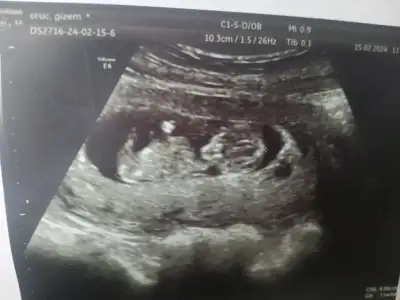

Çok sağol canım. TamamŞu parlak alan plesenta ise erkek diyorum. Normalde bebek sağda karın ultrasonu na göre solda görünse de plesenta solda gibi yani sağda karışık anlattım ama ben erkek diyorum bakalım ne çıkacak haber verirsin bize de